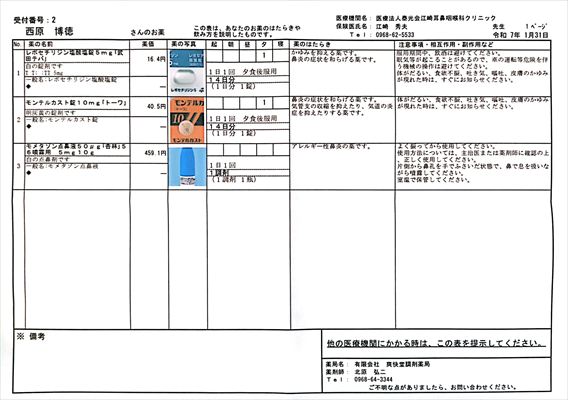

2025.1.31より 江崎耳鼻咽喉科 0968-62-5533

2025.1.31(金) 脳ドックによる副鼻腔炎の疑いから左目に涙が出る障害の件で受診

レントゲンによる検査で蓄膿症とまでは行っていない。左の鼻はかなり詰まっている。

採血によりアレルギー検査(大きな8項目)

レボセチリジン塩酸塩錠5mg「武田テバ」 モンテルカスト錠10mg「トーワ」